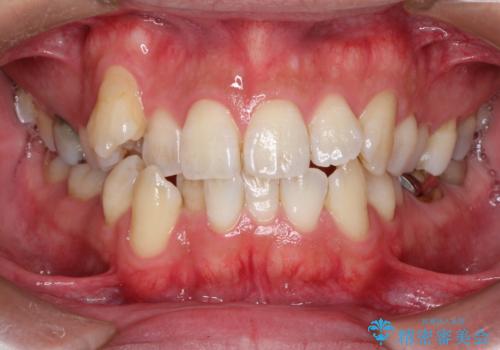

初診時の歯並びの状態としては、右上の犬歯がいわゆる八重歯の状態であり、強いガタガタが上下ともにある状態でした。

スペースの不足量が多く、抜歯を伴うワイヤー矯正にて治療を行いました。

若干の口元の突出感もあったため、抜歯によるスペースを利用し、がたつきの改善と前歯の後退をを行いました。